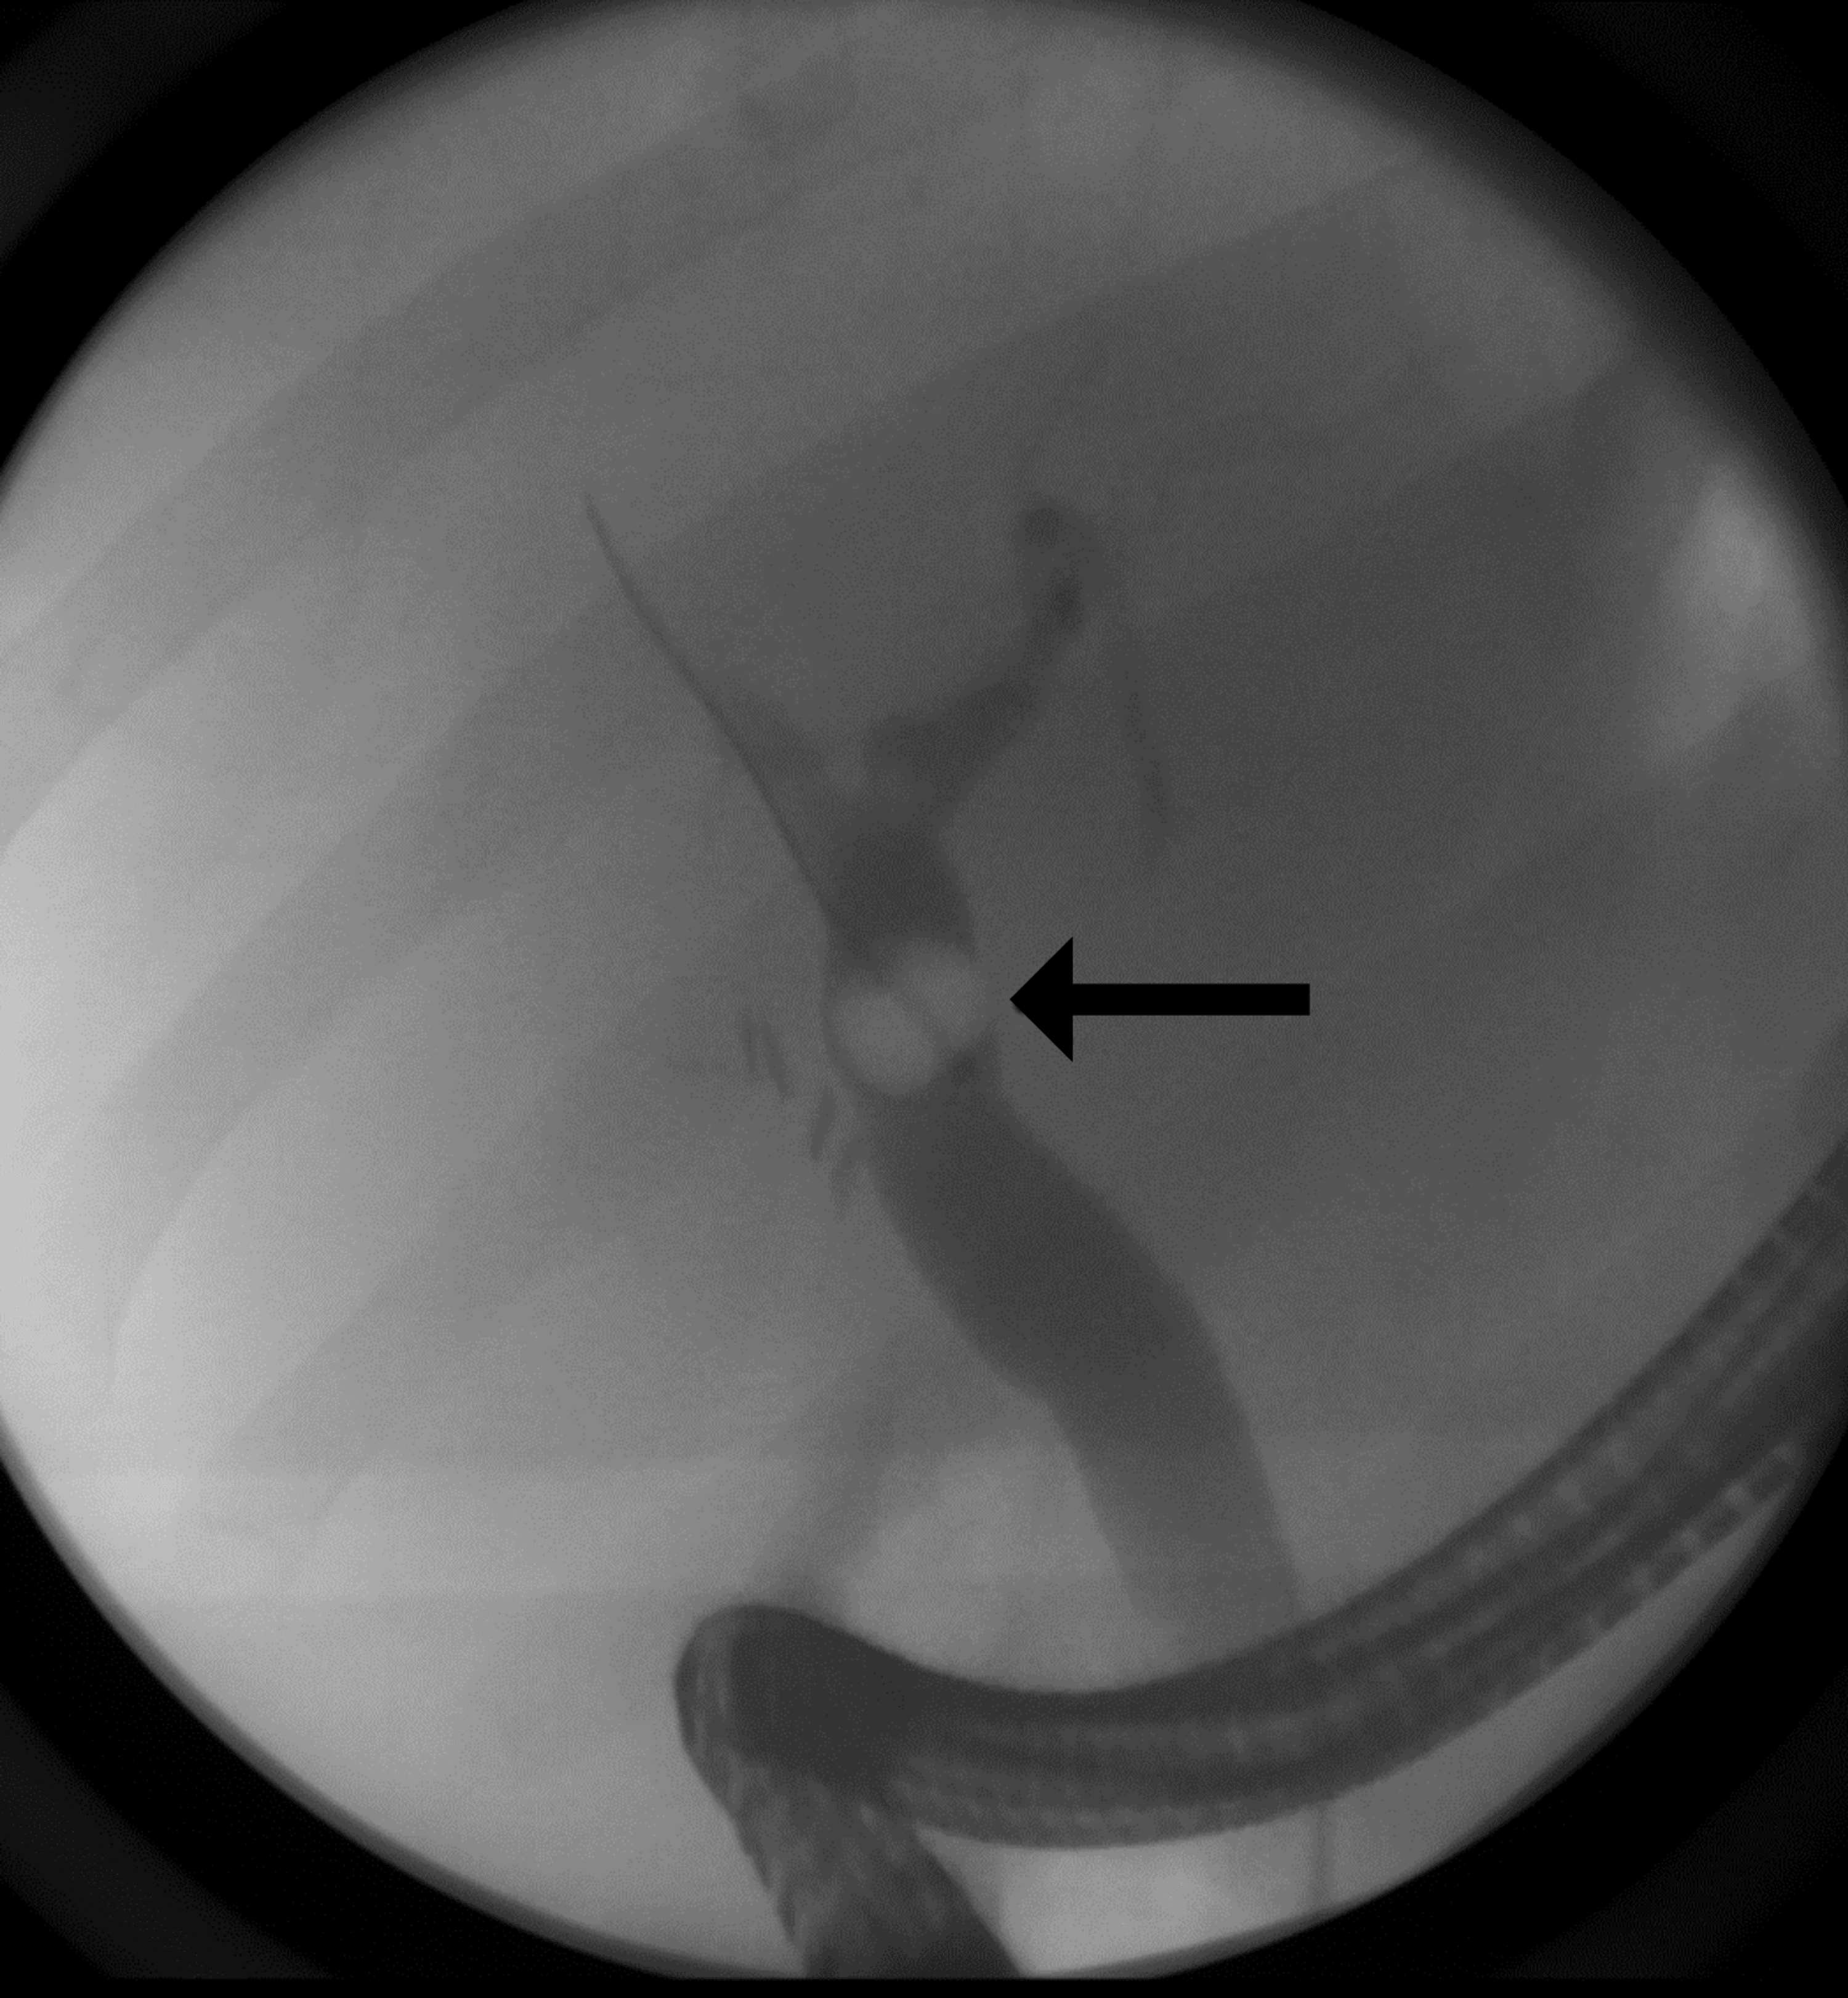

ERCP image of the gallstone (arrow) prior to removal. Download Ercp Gallstone Removal Recovery Recovery after ercp after ercp, you will be monitored while the sedative medications wear off. An ercp is used to diagnose and treat problems with your biliary system. Endoscopic retrograde cholangiopancreatography (ercp) confirms the diagnosis of choledocholithiasis, and ercp. Endoscopic retrograde cholangiopancreatography, or ercp, is a procedure to diagnose and treat problems in the liver, gallbladder, bile ducts, and. Ercp. Ercp Gallstone Removal Recovery.